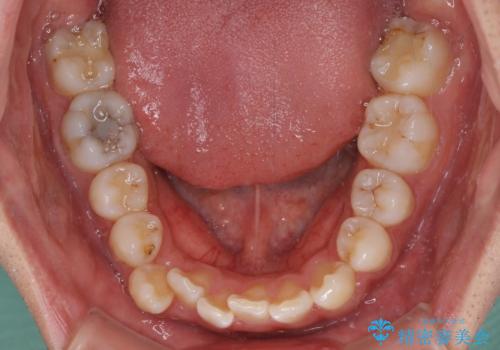

上下ともに八重歯が顕著であったため、上下左右の第一小臼歯4本を抜歯し、ワイヤー装置での抜歯矯正を行うこととしました。

前歯の歯列が整ったことで、歯磨きが大変やりやすくなり、患者様には大変満足していただけました。